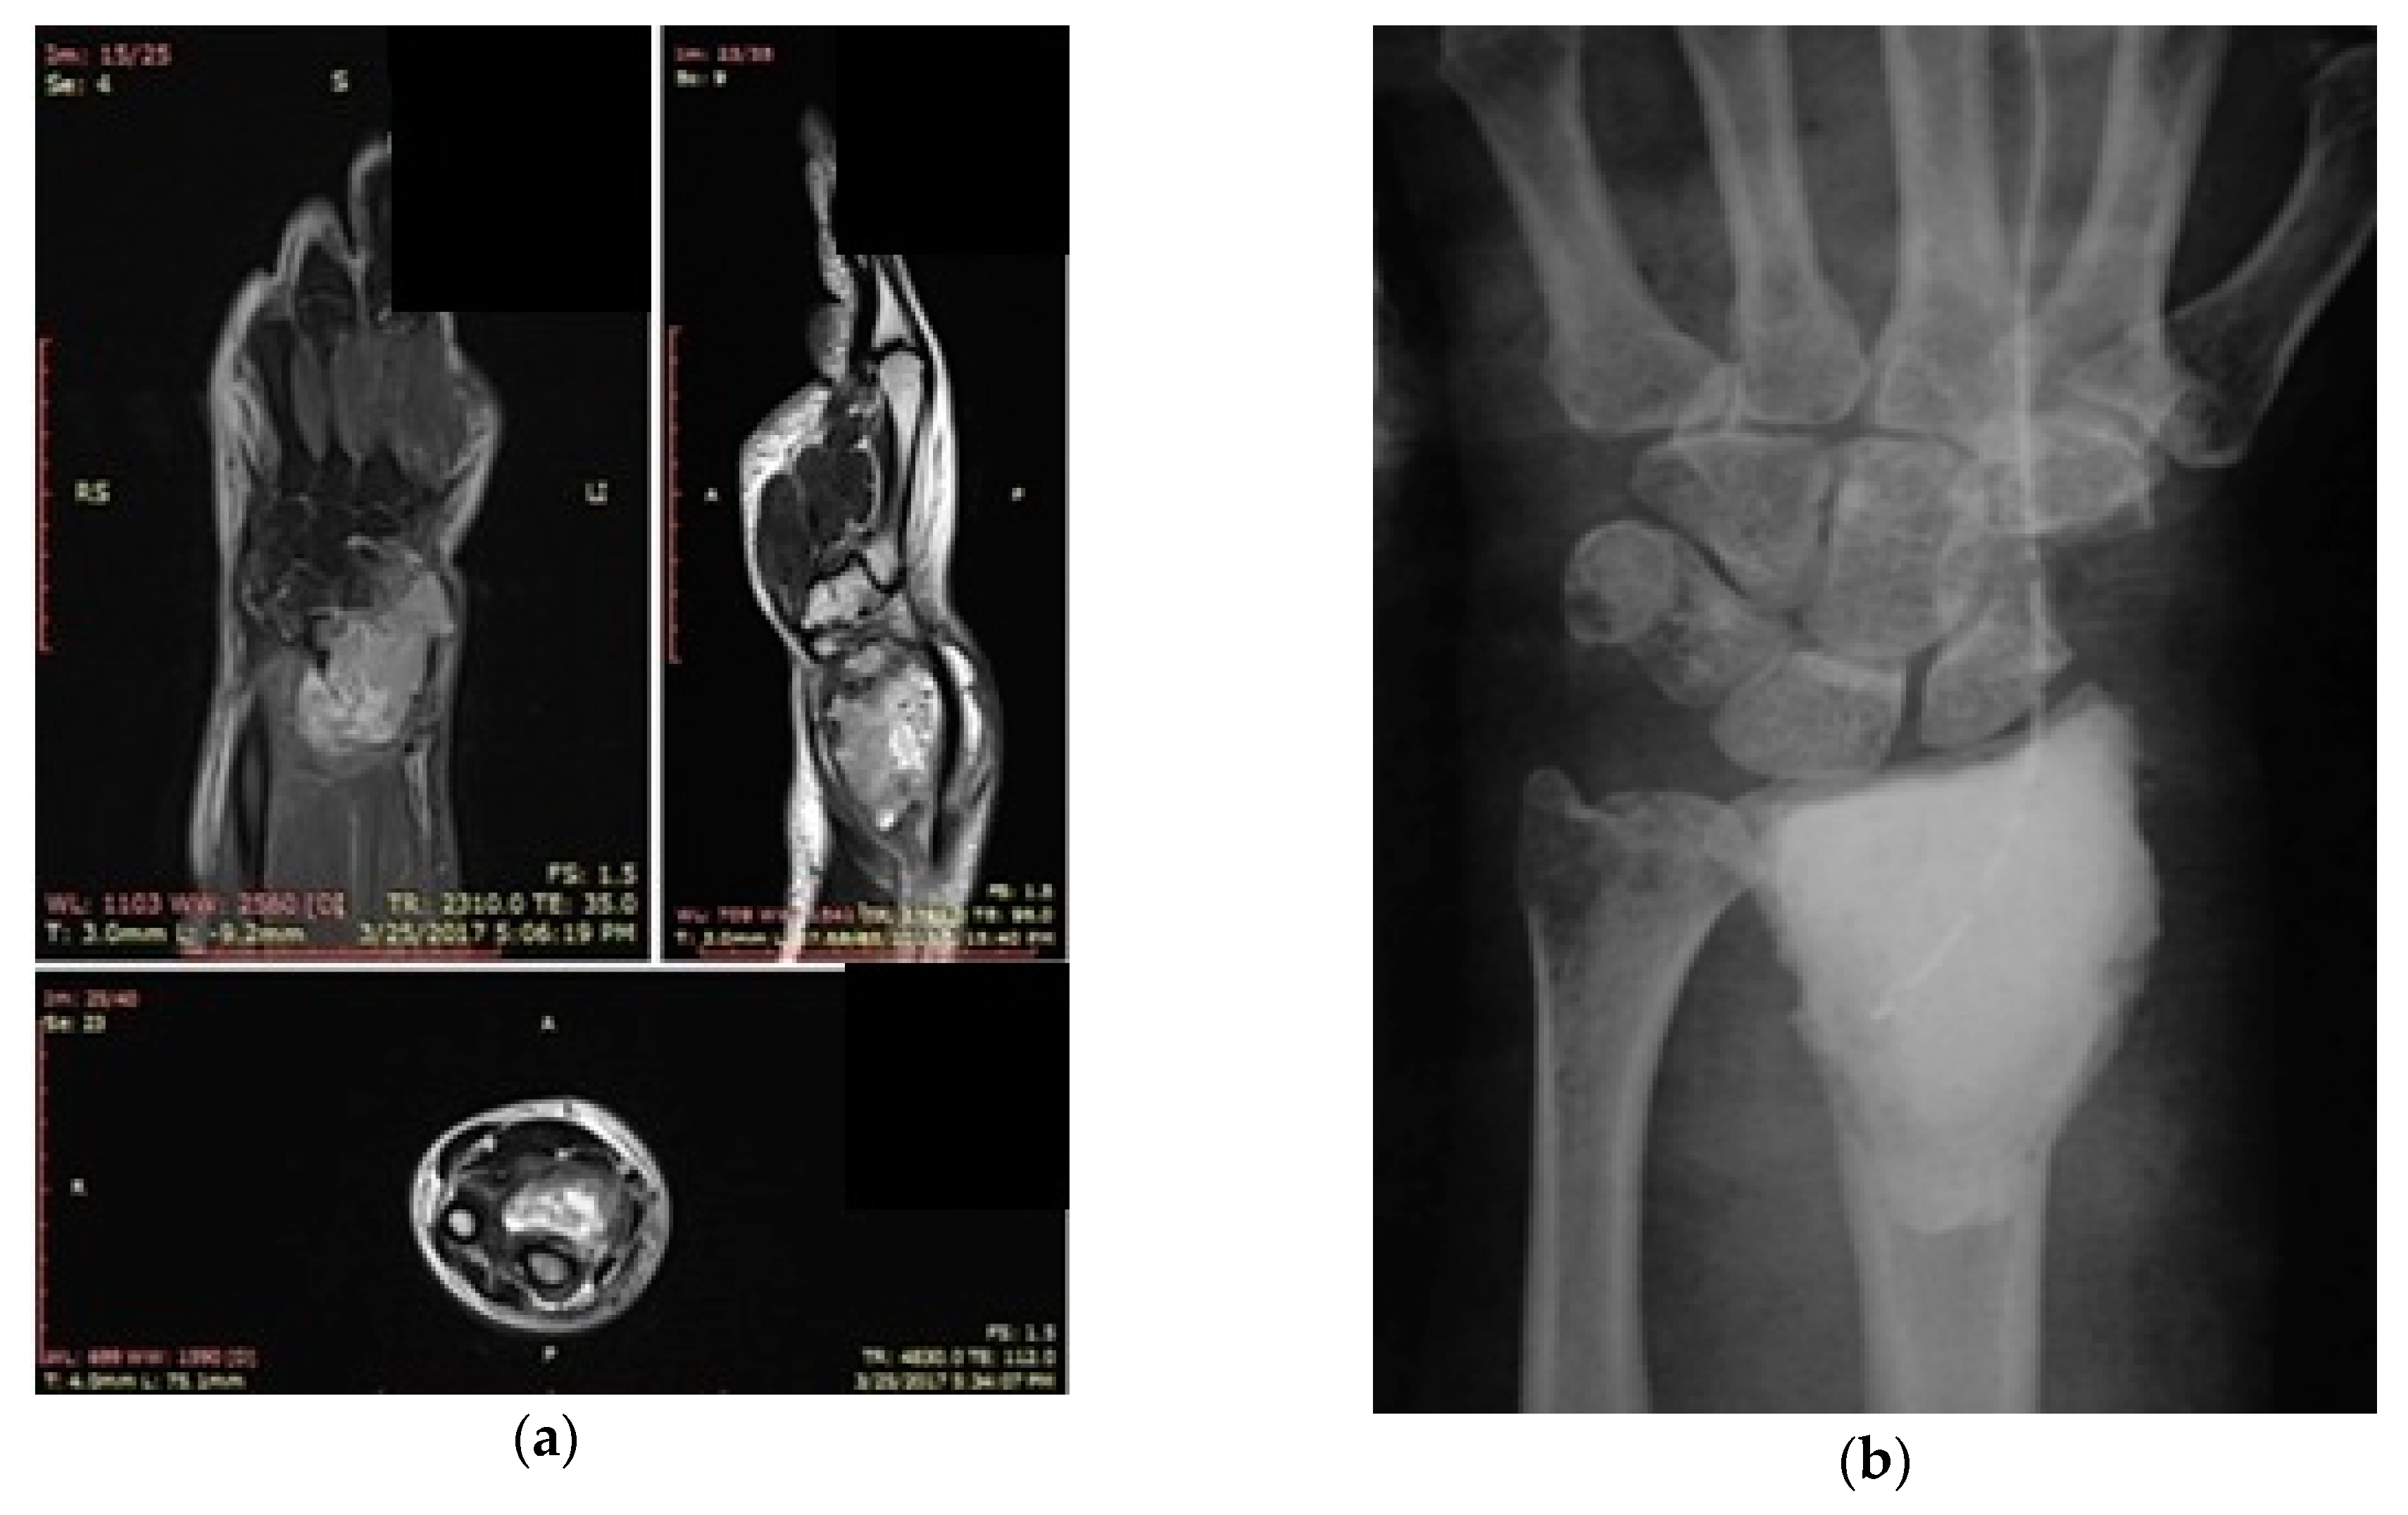

The second patient was a 61-year-old male with an osteolytic tumor of the right distal radius confirmed on the preoperative X-rays and MRI examinations (Figure 2a). Symptoms preceded the first radiological exam by two months (Figure 2b).

Case 2. (a) Preoperative MRI of the wrist joint (coronal, sagittal and axial) indicating GCT of distal radius. (b) Radiological exam of the wrist joint (AP view) one year after surgery reveals no sign of recurrence.

Histopathological results following a radiologically guided biopsy with a bone needle sustained the diagnosis of GCT. The same therapeutic protocol as in Case 1 was used, with complete resection of the tumor via a dorsal approach, including the biopsy site, followed by mechanical uniformization of the tumoral walls with the use of a high-speed ball-tipped burr. Extra care with the use of this device was required in the proximity of the subchondral region. Cryotherapy with LN was repeated twice following an adequate isolation of the soft tissues with warm saline-soaked gauze. Reconstruction of the subchondral region with a small amount of an iliac crest autograft was required and was followed by the filling of the remaining cavity with bone cement (PMMA). The senior surgeon appreciated that there was no use for additional plates and screw stabilization.

The postoperative functional result was fair (the disabilities of the arm, shoulder and hand-DASH score = 49), with mild pain at six months, restriction of flexion at 60° and neutral extension. No signs of recurrence were noted at the two-year follow-up (Figure 2b).